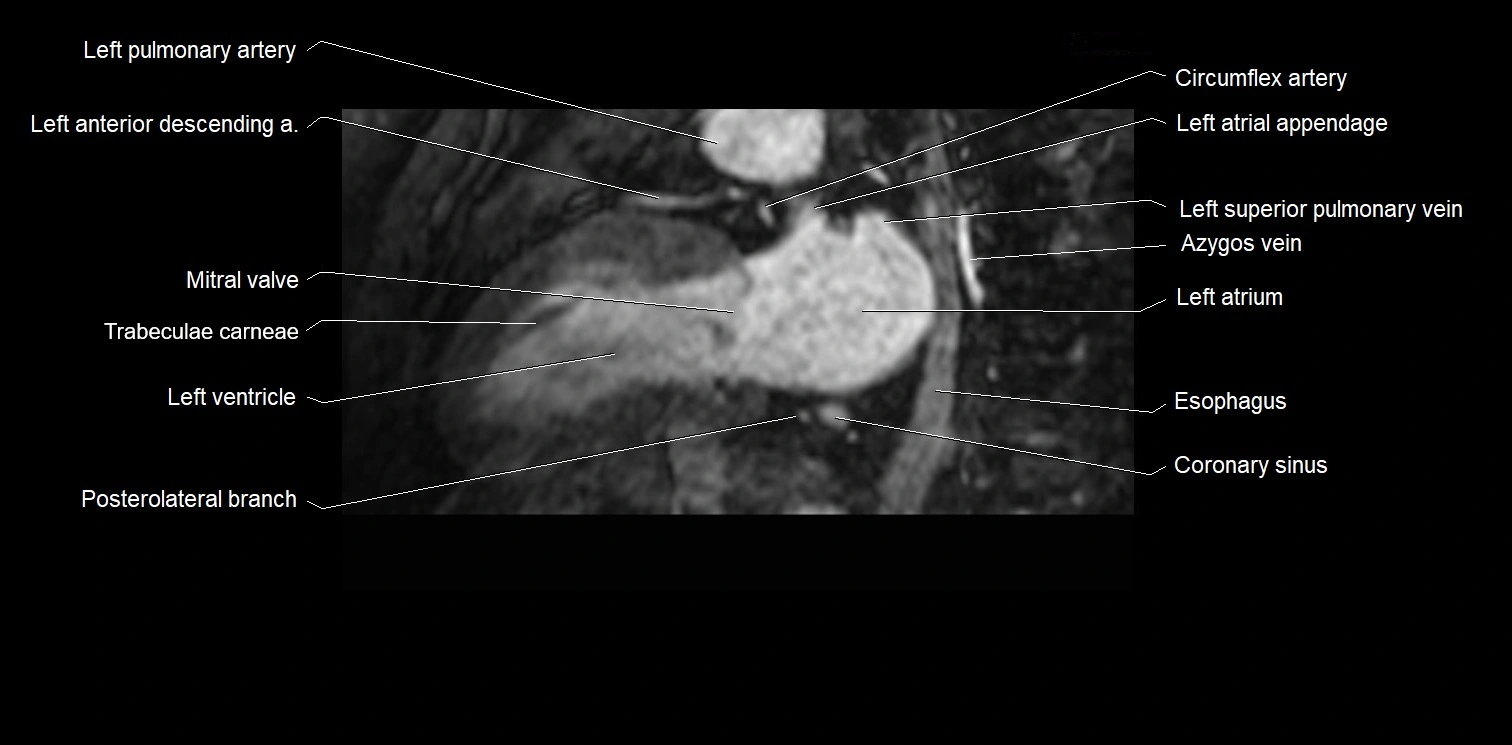

MRI image